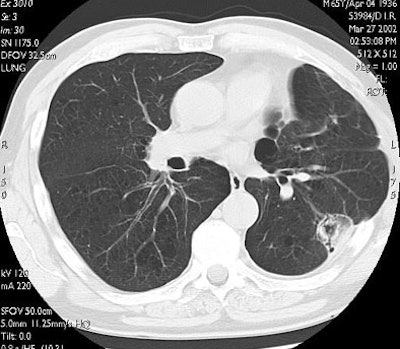

![]() |

| In the same patient, CT studies performed three months (above) and six months after treatment (below) show progressive shrinkage of the area of coagulation necrosis that exhibits central cavitation. No signs of tumor recurrence are detected. Images courtesy of Dr. Riccardo. |

"Here you can see one of the cases with a one-year follow-up. The tumor is replaced by a volume of coagulation, which is in excess with respect to the size of the native lesion, and then at three months, six months, and one year there is progressive shrinkage of the coagulation, with some cavitation detectable on CT," he said.